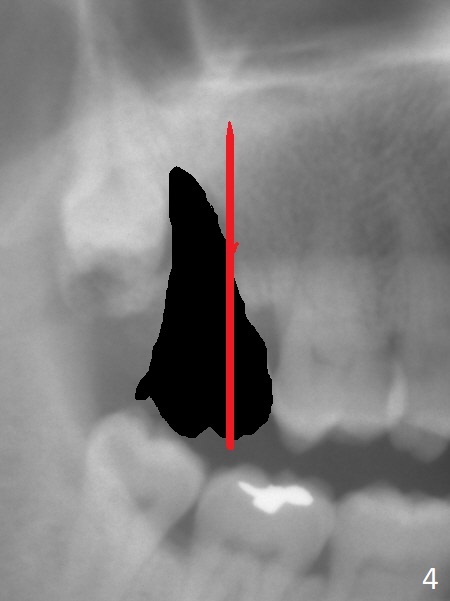

A 67-year-old man has pain associated with the tooth #2 with distal deep pockets (Fig.1), consistent with root fracture. The abnormal force may arise from the mesioangular lower 3rd molar (Fig.2 arrow). To avoid damage to the upper 3rd molar, osteotomy will be initiated obliquely with starter drill in the mesial slope of the socket (Fig.3 red). Once the starter drill makes a short entry, use 2 mm drill to change trajectory (Fig.4). Due to the uneven wall, an implant is expected to be placed distally by itself (Fig.5). The bone height is ~18 mm. If the patient agrees, remove the lower 3rd molar (Fig.5 black area).